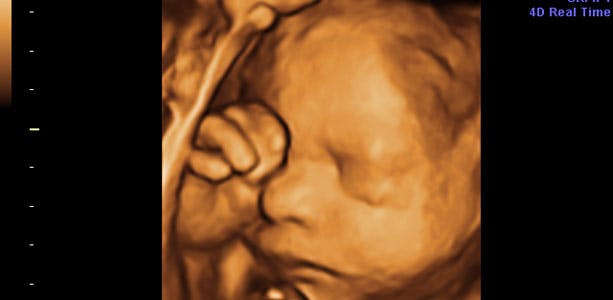

Gravid uge 30: Laver vejrtrækningsøvelser

Lungerne er næsten helt modne, og baby øver sig ihærdigt i at lave vejrtrækningsøvelser. Måske er det derfor, du fra tid til anden kan opleve små rytmiske bevægelser i maven, når det får hikke. Hikke er helt normalt og påvirker ikke din baby på nogen måde. I slutningen af ugen måler baby cirka 37 centimeter og vejer omkring 1550 gram. Lårbenet måler 5,6 cm, maveomkredsen 26,5 centimeter og hovedet 7,7 centimeter i diameter.